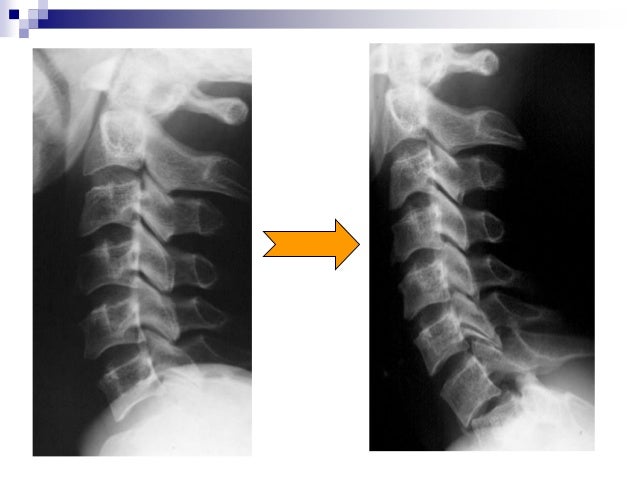

Fracture Luxation Et Entorse Du Rachis Cervical Thoracotomie

5 Traumatisme Du Rachis Cervical Moyen Et Inferieur Medicine Key